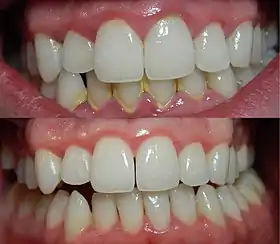

![]() | |

| A severe case of gingivitis | |